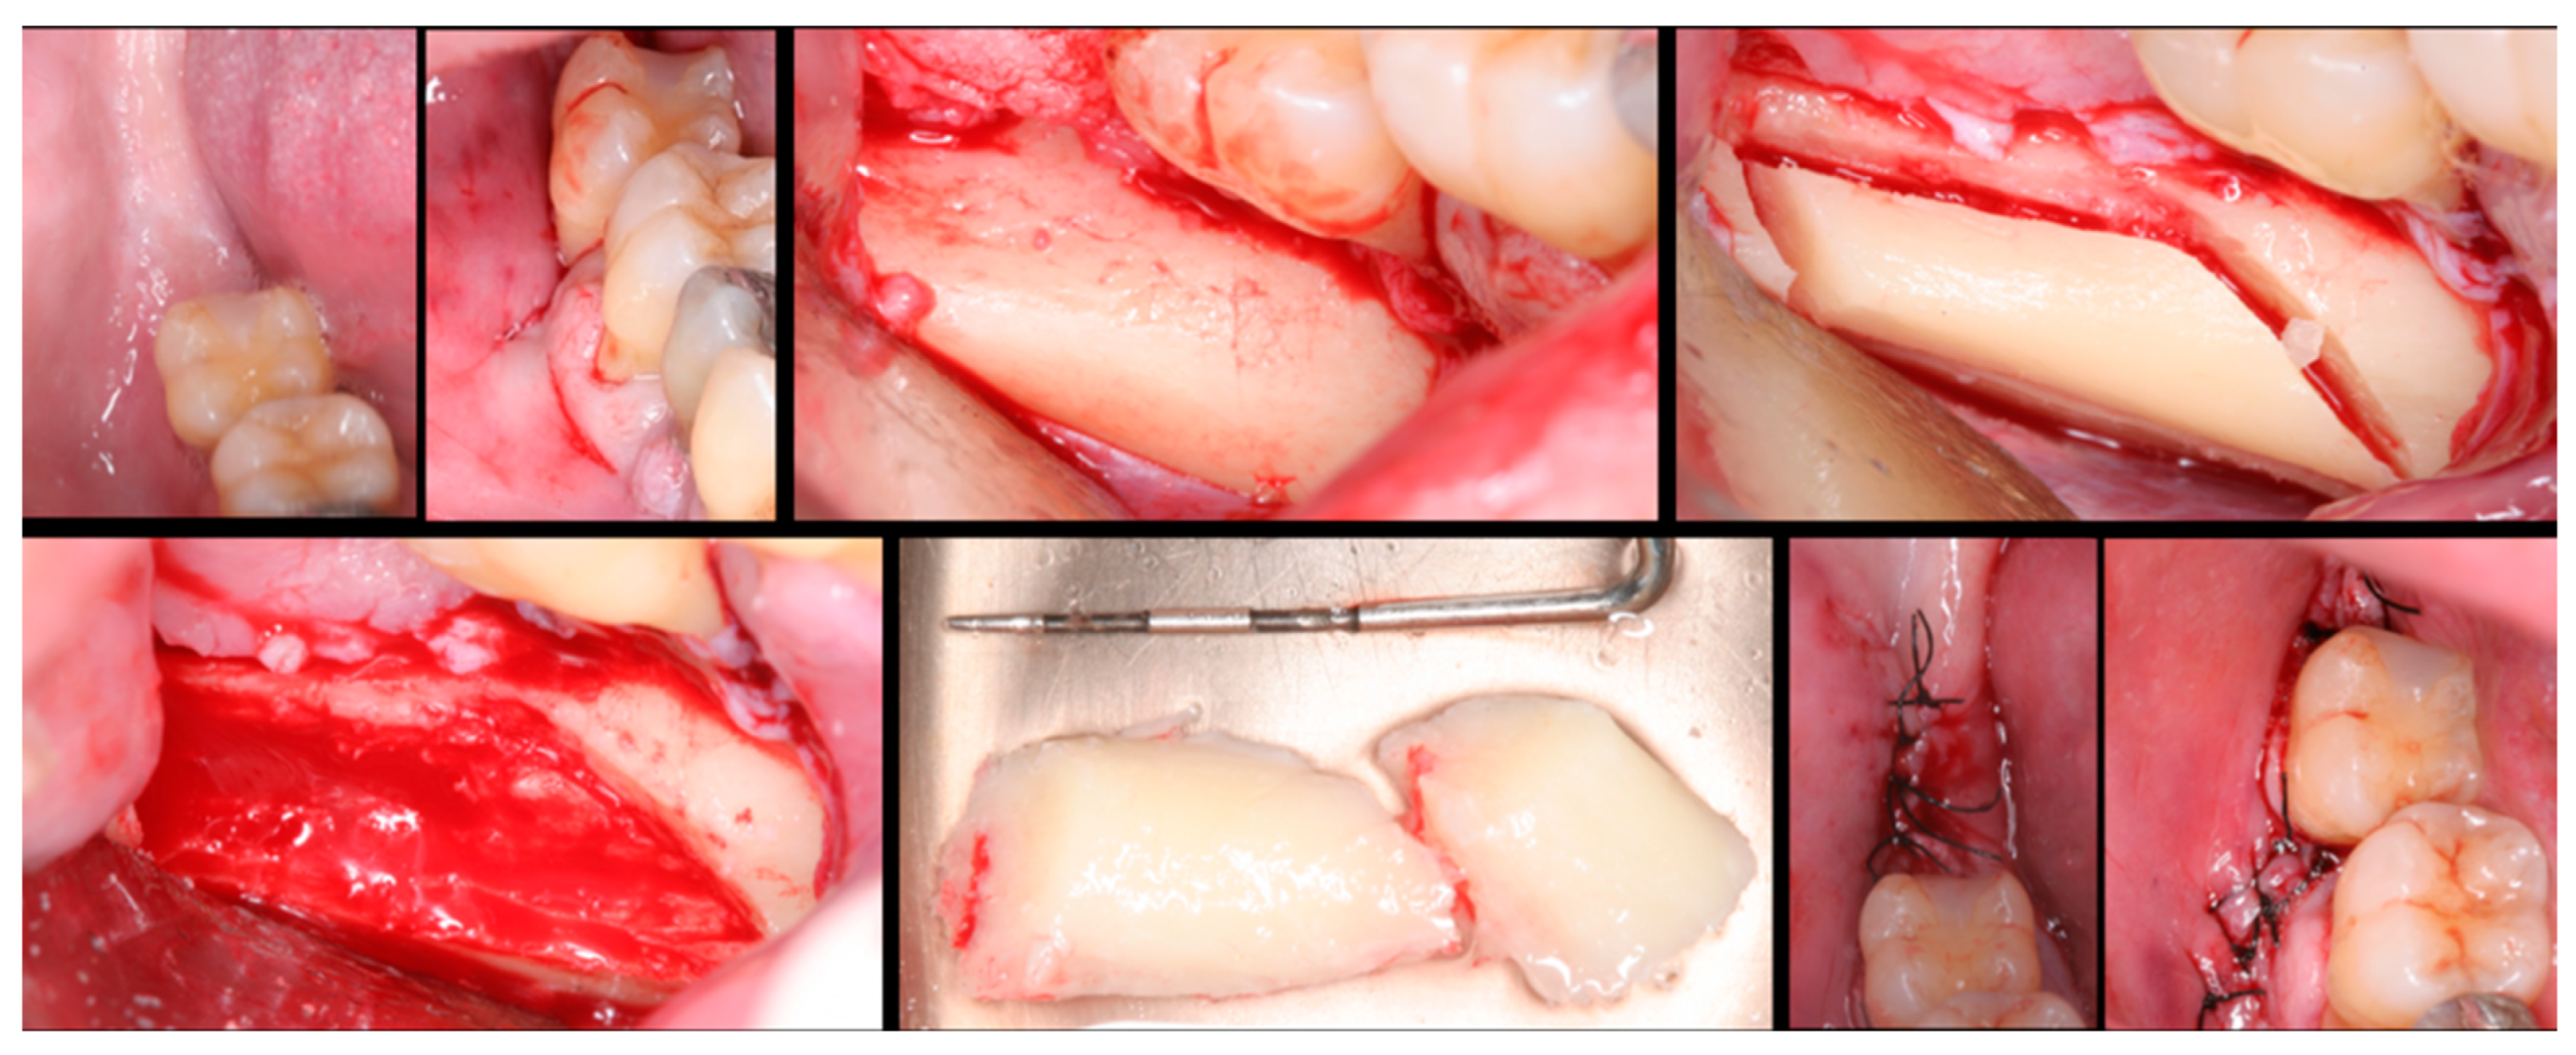

The surgical process, performed by the same surgeon, involved local anesthesia followed by incisions, flap detachment, osteotomy, and membrane elevation. Autologous bone from the mandibular branch (Figure 1) or the mental symphysis (Figure 2), or a porcine xenograft (Figure 3) were used as the graft materials for sinus augmentation. The protocol for this study involved using either two or three syringes of Oteobiol MP3, delivering a volume of approximately 2 to 3 cc per sinus. The contralateral sinus received a similar amount of autologous bone, either from the mental region (desmal with probably some bone of enchondral origin) or the mandibular ramus (desmal origin). Figure 3 and Figure 4 depict one example from each side of maxillary sinus augmentation treatment. Post surgery, the patients followed a prescribed protocol. After six months, a follow-up CT scan was conducted, and dental implants were placed. The final phase involved inserting healing abutments or prostheses, ensuring that no tooth–implant connections were established [20].

Figure 3. Step-by-step surgical demonstration of maxillary sinus elevation with xenograft. In the first row, left to right: incision in the fourth quadrant, flap detachment, and lateral osteotomy. In the second row, left to right: accessing the sinus, filling with xenograft, collagen membrane positioning, and sutures.